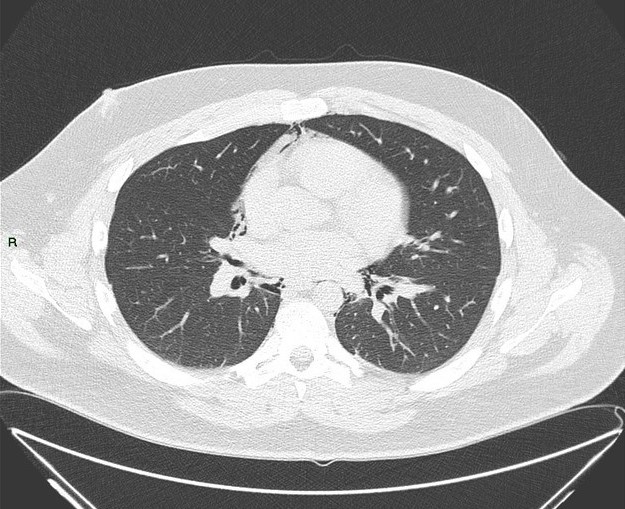

Tràn khí trung thất

Tràn khí trung thất - Ảnh 2

» Thông tin: Nam giới – 25 tuổi.

» Lâm sàng: Đau ngực.